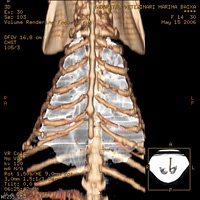

Tórax:

Abdomen: